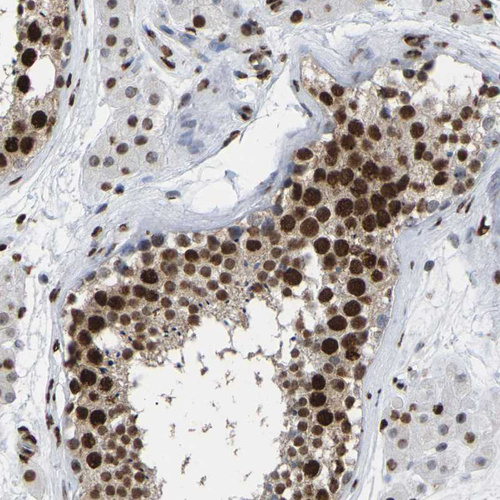

Immunohistochemical staining of human testis shows strong nuclear positivity in cells in seminiferous ducts.